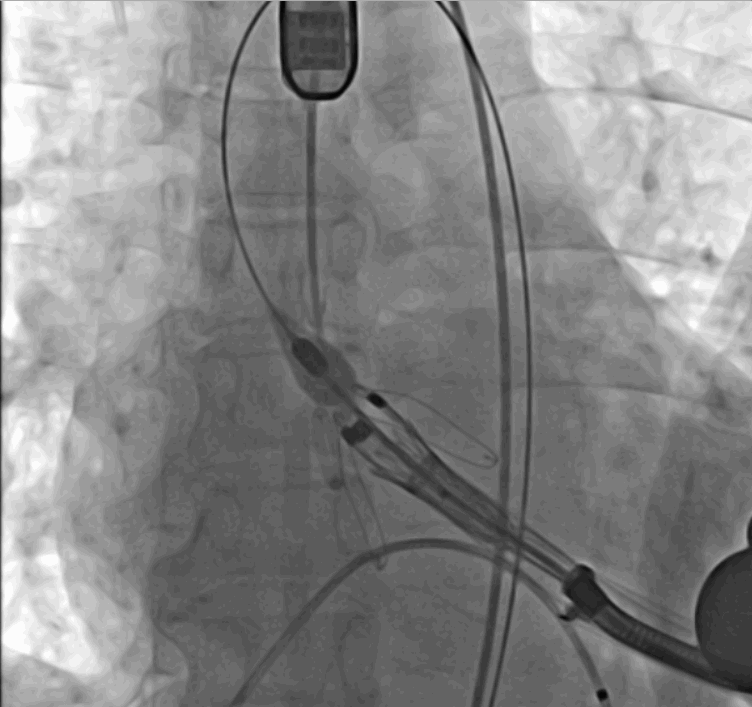

手術(shù)采用經(jīng)心尖入路,對患者進(jìn)行全麻后,在左側(cè)心尖處做3-4cm微創(chuàng)手術(shù)切口,在DSA及超聲引導(dǎo)下手術(shù)順利完成。從導(dǎo)入器械到完成瓣膜置入,僅耗時約10分鐘。術(shù)后即刻主動脈瓣返流程度由術(shù)前大量返流轉(zhuǎn)為消失,患者于導(dǎo)管室拔除氣管插管,次日由ICU轉(zhuǎn)入普通病房。

術(shù)前DSA影像圖